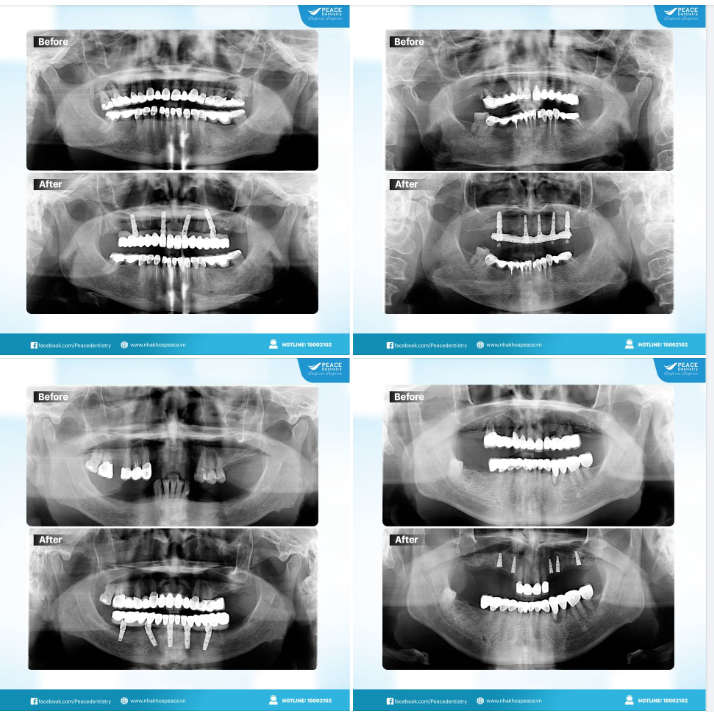

Khách hàng trên 50 tuổi đến Peace Dentistry với tình trạng: mất nhiều răng ở cả 2 hàm và đang sử dụng các ??̂̀? ??̆?? ??̛́ ??̀? ???̛?? đ?̃ ??? ???̉? ??̃ ??̣̂? ???̛́? ??̆?? ?̆? ???? ??̀ ???̂̉? ??̃ → sức nhai yếu, tụt nướu, khoảng hở giữa cầu răng sứ và nướu gây nhét thức ăn, hôi miệng. Ngoài ra, cầu răng sứ đã suy giảm tính thẩm mỹ.

MỤC TIÊU ĐIỀU TRỊ: khôi phục trọn vẹn chức năng ăn nhai và thẩm mỹ cho khách hàng, đồng thơi vẫn giữ lại các cùi răng thật theo mong muốn của khách hàng, chi phí tối ưu nhất.

CHỈ ĐỊNH ĐIỀU TRỊ CHÍNH:

✓ Tháo bỏ toàn bộ cầu răng sứ và mão sứ ở cả 2 hàm;

✓ Cấy 5 trụ Implant hàm trên & 3 Implant hàm dưới;

✓ Bọc lại răng sứ cho các răng còn lại

KẾT QUẢ SAU ĐIỀU TRỊ:

Răng 2 hàm được khôi phục với chức năng ăn nhai khỏe, thẩm mỹ cao, cảm giác răng miệng thoải mái; Dự báo: sử dụng rất lâu dài, nếu chăm sóc răng tốt sẽ sử dụng đến trọn đời.